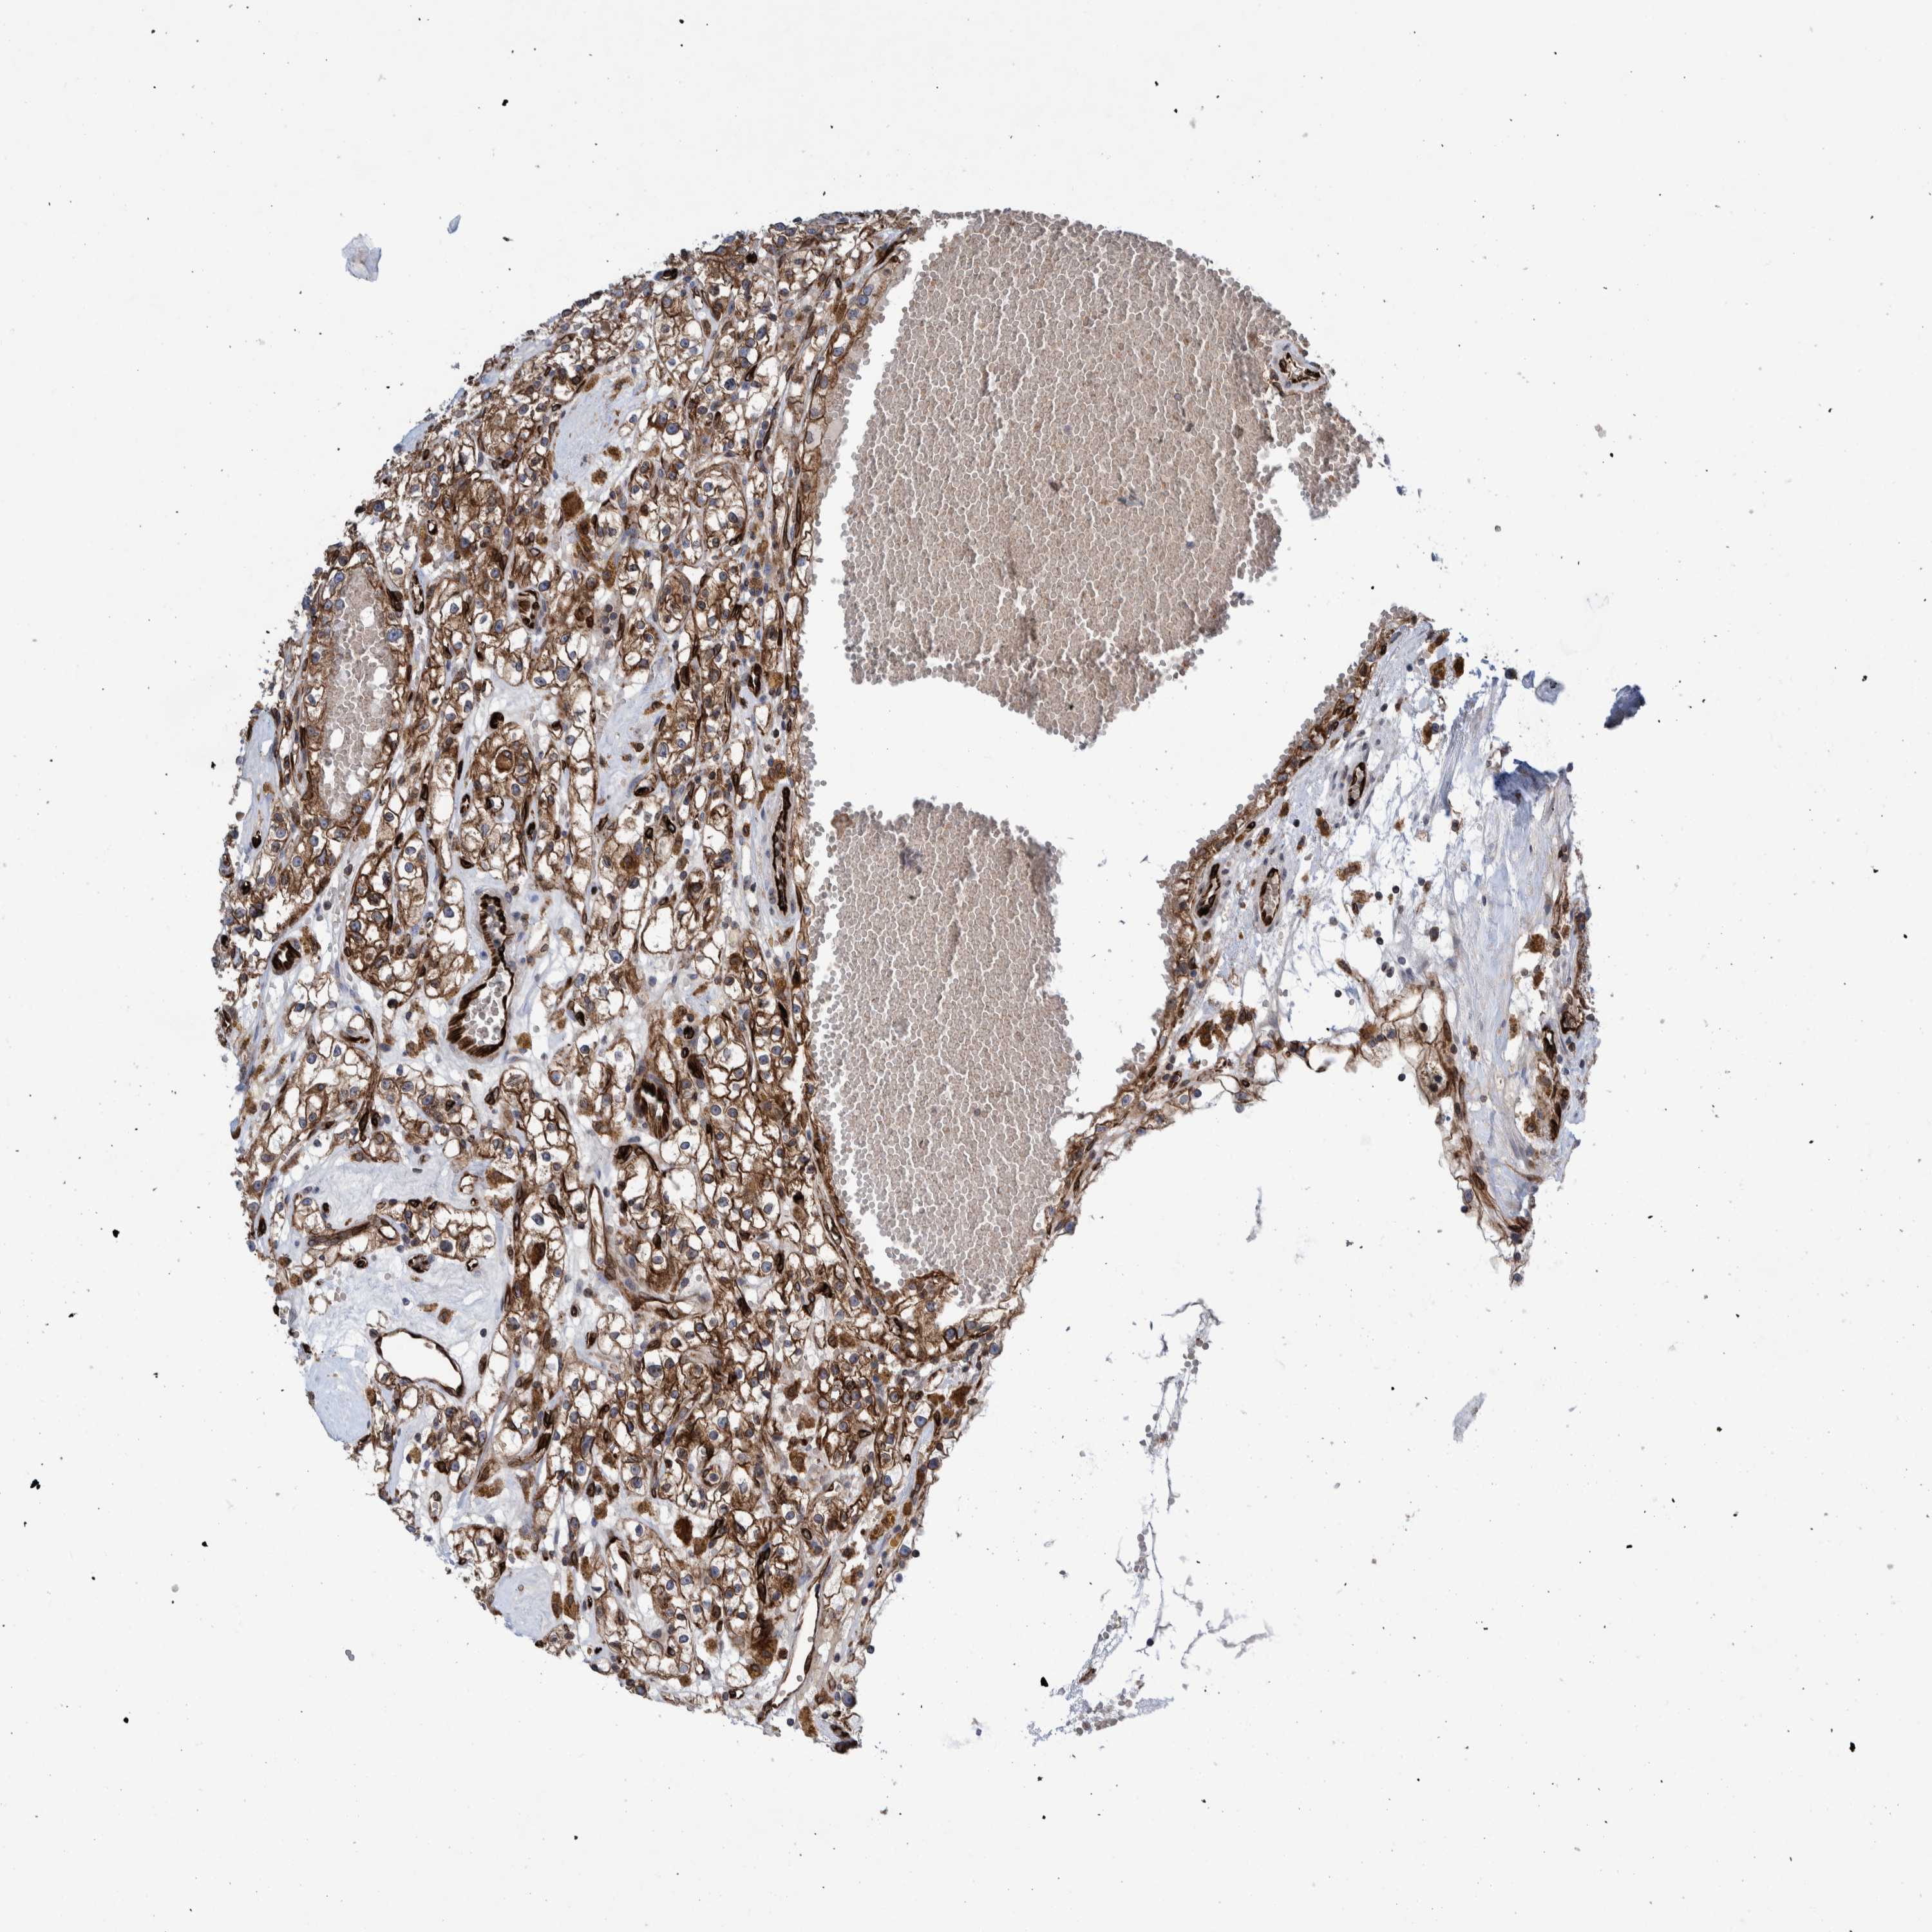

KIDNEY RENAL CLEAR CELL CARCINOMA (VALIDATION) - Interactive survival scatter ploti

The Survival Scatter plot shows the clinical status (i.e. dead or alive) for all individuals in the patient cohort, based on the same data that underlies the corresponding Kaplan-Meier plots. Patients that are alive at last time for follow-up are shown in blue and patients who have died during the study are shown in red.

The x-axis shows the expression levels (FPKM) of the investigated gene in the tumor tissue at the time of diagnosis. The y-axis shows the follow-up time after diagnosis (years). Both axes are complimented with kernel density curves demonstrating the data density over the axes. The top density plot shows the expression levels (FPKM) distribution among dead (red) and alive patients (blue). The right density plot shows the data density of the survived years of dead patients with high and low expression levels respectively, stratified using the cutoff indicated by the vertical dashed line through the Survival Scatter plot. This cutoff is automatically defined based on the FPKM cutoff that minimizes the p-score. The cutoff can be changed by dragging the vertical line or by entering a cutoff value in the square labeled "Current cut-off".

Under the Survival Scatter plot the p-score landscape (black curve; left axis) is shown together with dead median separation (red curve; right axis). Dead median separation is the difference in median mRNA expression between patients who have died with high and low expression, respectively. It is calculated as follows: median FPKM expression of dead patients with high expression - median FPKM expression of dead patients with low expression. This is intended to aid the user in visually exploring custom cutoffs and the associated p-scores and dead median separation.

Individual patient data is displayed and can be filtered by clicking on one or more of the category buttons on the top of the page. Categories describing expression level and patient information include: high, low, alive, dead, female, male and tumor stages. The scale of the x-axis can be toggled between linear and log-scale by clicking on the "x log" button. Mouse-over function shows TCGA ID, patient information and mRNA expression (FPKM) for each patient.

& Survival analysisi

Kaplan-Meier plots summarize results from analysis of correlation between mRNA expression level and patient survival. Patients were divided based on level of expression into one of the two groups "low" (under cut off) or "high" (over cut off). X-axis shows time for survival (years) and y-axis shows the probability of survival, where 1.0 corresponds to 100 percent.

THEM6 is not prognostic in Kidney Renal Clear Cell Carcinoma (validation)

Best expression cut offi

Based on the FPKM value of each gene, patients were classified into two groups and association between prognosis (survival) and gene expression (FPKM) was examined. The best expression cut-off refers the FPKM value that yields maximal difference with regard to survival between the two groups at the lowest log-rank P-value. Best expression cut-off was selected based on survival analysis .

When clicking on this number, the vertical dashed line indicating cut-off, the interactive survival plot, and the Kaplan-Meier curve will be adjusted to show results based on the best expression cut-off.

: 16.66

TCGA RNA samplesi

RNA-seq data is reported as average FPKM (number Fragments Per Kilobase of exon per Million reads), generated by the The Cancer Genome Atlas (TCGA) .

Normal distribution across the dataset is visualized with box plots, shown as median and 25th and 75th percentiles. Points are displayed as outliers if they are above or below 1.5 times the interquartile range. FPKM values of the individual samples are presented next to the box plot.

Average pTPM 24.8

Number of samples 100